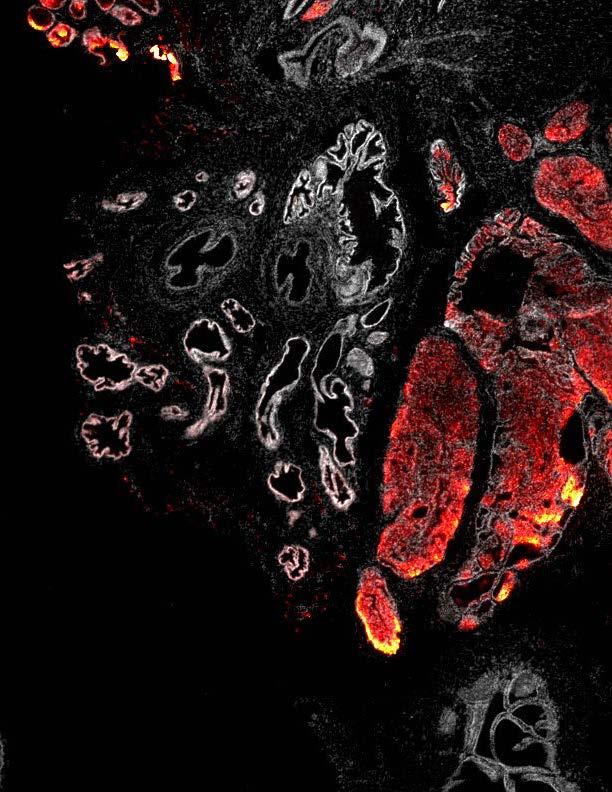

New research represents a promising step towards better understanding of a key cancer gene. A long-running collaboration between researchers at the Babraham Institute, Cambridge and the AstraZeneca IMED Biotech Unit reveals new insights into how the PTEN gene may control cell growth and behaviour and how its loss contributes to the development and advancement of certain cancers.

PTEN is reportedly the second most commonly altered gene in human cancers. The study, led by Dr Len Stephens and Dr Phill Hawkins and published today in the journal Molecular Cell , reveals why loss of the PTEN gene has such an impact on many people with prostate cancer, as well as in some breast cancers. These results, which also include work from Akita University, Japan, and contributions from GSK could help to identify patients likely to benefit from novel targeted therapies.

PTEN is known as a tumour suppressor gene meaning that it typically slows the growth of cells and its loss can lead to cancer. By regulating the levels of the chemical phosphatidylinositol-3,4,5-trisphosphate (PI(3,4,5)P3), PTEN helps to limit cell growth and so prevents cancer.

Yet, the new paper shows that this is only part of the story. The team at the Institute, supported by GSK and together with AstraZeneca have identified another way that PTEN may prevent uncontrolled cell growth. PTEN can also reduce the levels of another similar molecule known as phosphatidylinositol-3,4-bisphosphate (PI(3,4)P2). The role of PI(3,4)P2 is still becoming clear but it may be able to alter the activity of the AKT protein, a key regulator of cell growth. PI(3,4)P2 may also influence several other proteins that regulate the process of invasion; how cancer cells spread and move through the body.

By studying human cancer cells and animal models of cancer in the lab, our researchers have shown that loss of PTEN leads to high levels of PI(3,4)P2, which could result in hyperactivation of AKT. This may indicate AKT as an effective target for new cancer treatments. AstraZeneca's AKT inhibitor is currently in clinical trials for prostate, breast and other cancers. This collaboration could help to devise tests to identify patients who will benefit from these targeted therapies.